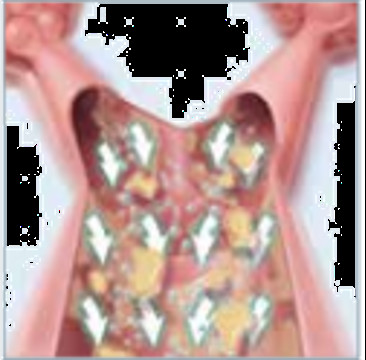

Portable Healthcare Vest Airway Clearance System Cough Assist For Child& Adult

Portable Healthcare Vest Airway Clearance System Devices 220V Images |